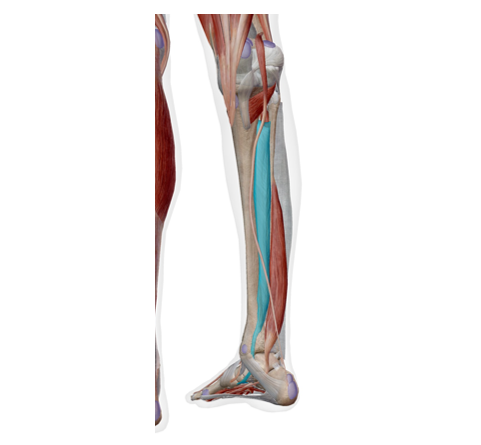

足首の内側の痛みでかなり多いのが、後脛骨筋腱(こうけいこつきんけん)の炎症です。

後脛骨筋は、足の内側に付いていて土踏まずを支える重要な筋肉です。

後脛骨筋は上の写真のように付着しています。よく見ると、足の裏の方まで続いていますね。

後脛骨筋は、土踏まずを支える筋肉です。

後脛骨筋は、足首を内側へ動かす筋肉でもあります。